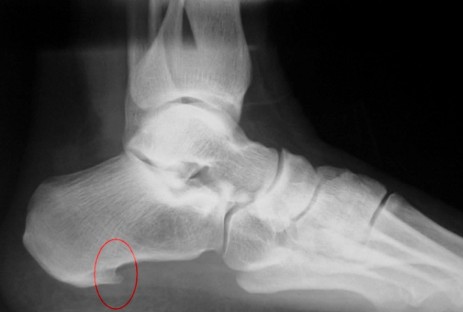

El Consultorio Médico Podológico Dr. Angee la aplica en el manejo de la Fascitis plantar (Espolón Calcáneo).